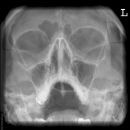

Nasennebenhöhlen (NNH)

Indikation

Sinusitis, Z. n. Osteosynthese

Lagerung

sitzend mit Gesicht zum Stativ

Hände festhaltend am Stativ

Rücken gerade

Mund weit geöffnet

Kinn liegt auf, Nase schwebt

Kopf anheben bis obere Zahnreihe und 1 QF über Ohr-Rand eine Linie bilden

Zentralstrahl

Querstrahl: 1 QF über oberen Ohrrand & Oberlippe

Längsstrahl: Medianebene

Einblendung

lateral auf Augenwinkel, cranial: auf Haaransatz

Anmerkung

Besonders auf symmetrische Lagerung achten. Im Sitzen ist evtl. Flüssigkeitsspiegel gut beurteilbar.

Qualitätskriterien

Symmetrische Darstellung des Gesichtsschädels: seitengleiche Distanz zwischen lateralem Rand der Augenhöhle und äußerer Schädelkontur. Die Pyramidenoberkanten kommen unmittelbar unterhalb des Kieferhöhlenbodens zum Liegen, also in die obere Zahnreihe, sodass die Kieferhöhlen überlagerungsfrei zur Darstellung kommen.